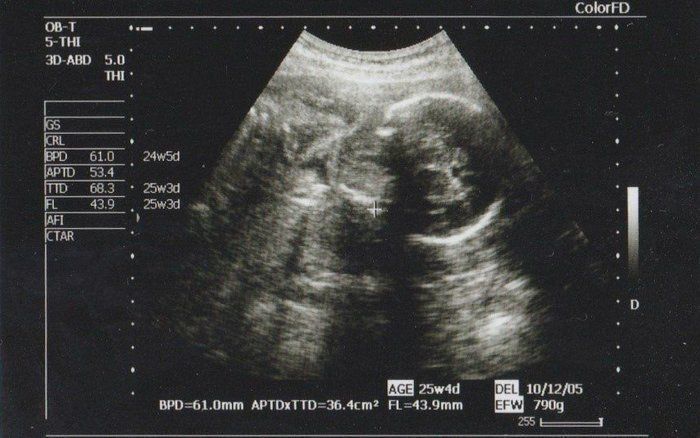

チャーミー小結さんの妊娠24週目のエコー写真

2D画像。医師から「今、性別を知りたいですか?それとも楽しみに取っておきますか?」と尋ねられ、名付けや準備に必要だからと教えてもらいました。前夜にみた夢のお告げ通りだったので、ますます神秘的な気持ちになりました。